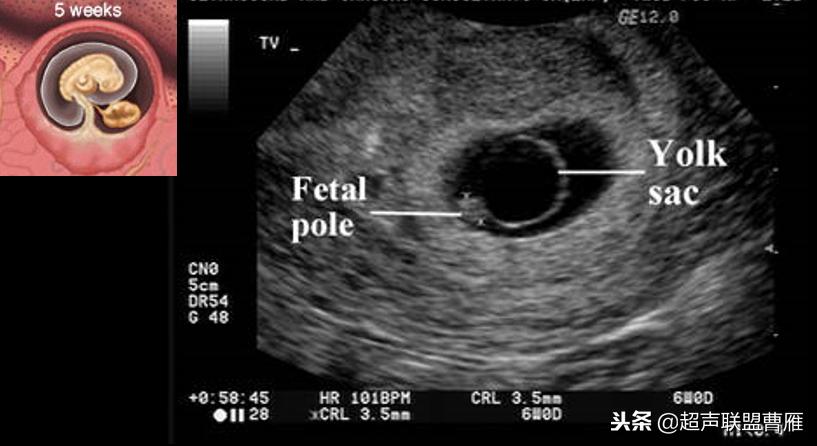

妊娠40天,见到卵黄囊、胚极及心管搏动, HCG12800U/L。

妊娠35天,高分辨的超声检查就可能见到心管搏动、胚极及卵黄囊。

· 正常卵黄囊内径一般在3-5mm,妊娠第5-10周逐渐增大,而10周后逐渐减小,一般12周前消失。

· 当妊娠囊平均直径在5-6mm时,经阴道超声即可发现卵黄囊